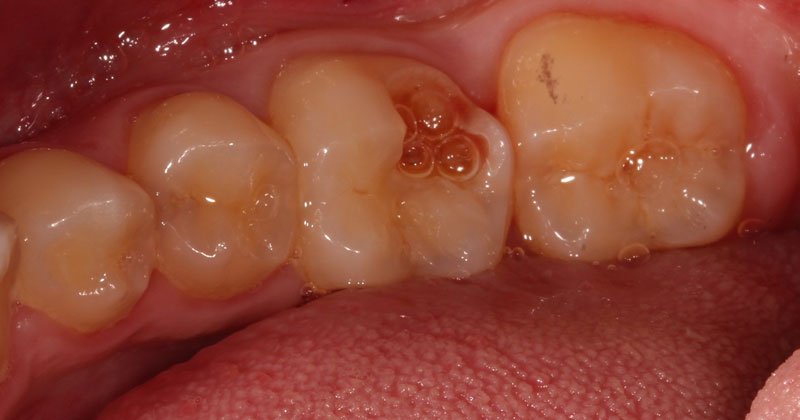

Management and restoration of deep carious lesions can be a challenging dilemma faced in our daily practice. In a previous article, I briefly highlighted considerations when managing deep carious lesions. One of the considerations was whether or not to perform a pulp cap prior to restoring a tooth with a deep carious lesion.

Pulp capping can be divided into two categories: indirect pulp capping and direct pulp capping. For an indirect pulp cap, a carious lesion approaches the pulp tissue, but a pulp exposure does not occur. With a direct pulp cap, the pulpal tissue is exposed, and a medicament is placed over the exposure. Both procedures have historically been controversial. However, with a greater focus on conservative dentistry and more research on pulp capping, this topic is being discussed more frequently.

A direct pulp cap exposes a portion of the pulp tissue. This can occur due to traumatic or carious pulp exposures. In the past, when a tooth’s pulp was exposed, it almost always led to endodontic therapy. However, direct pulp capping may be feasible in specific clinical situations with modern materials that can help maintain pulp vitality, such as MTA and similar bioceramics.